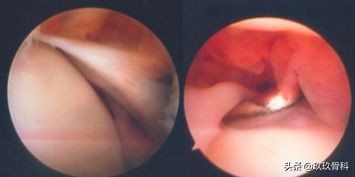

抽屉试验

术中抽屉试验

内翻应力试验